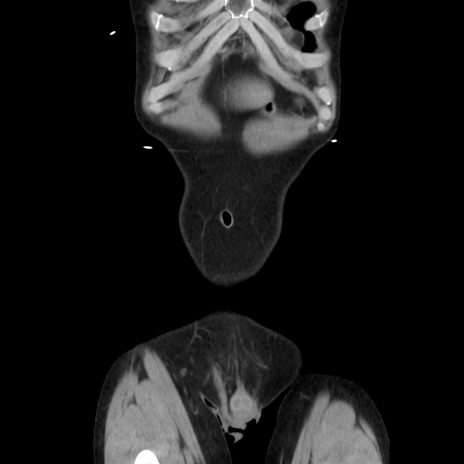

症例37(冠状断像)

【症例】40歳代 男性

【主訴】腹痛

【現病歴】4時間ほど前に電車に乗車中に臍部上より腹痛出現。徐々に増悪し起立困難となり、救急外来受診。生ものは数日食べていない。今朝お雑煮を食べた。

【身体所見】BT 36.8℃、BP 117/84mmHg、HR 91/min、SpO2 97%、苦悶様、腹部:臍上部広範囲圧痛あり、反跳痛±

【データ】WBC 8100、CRP 0.03